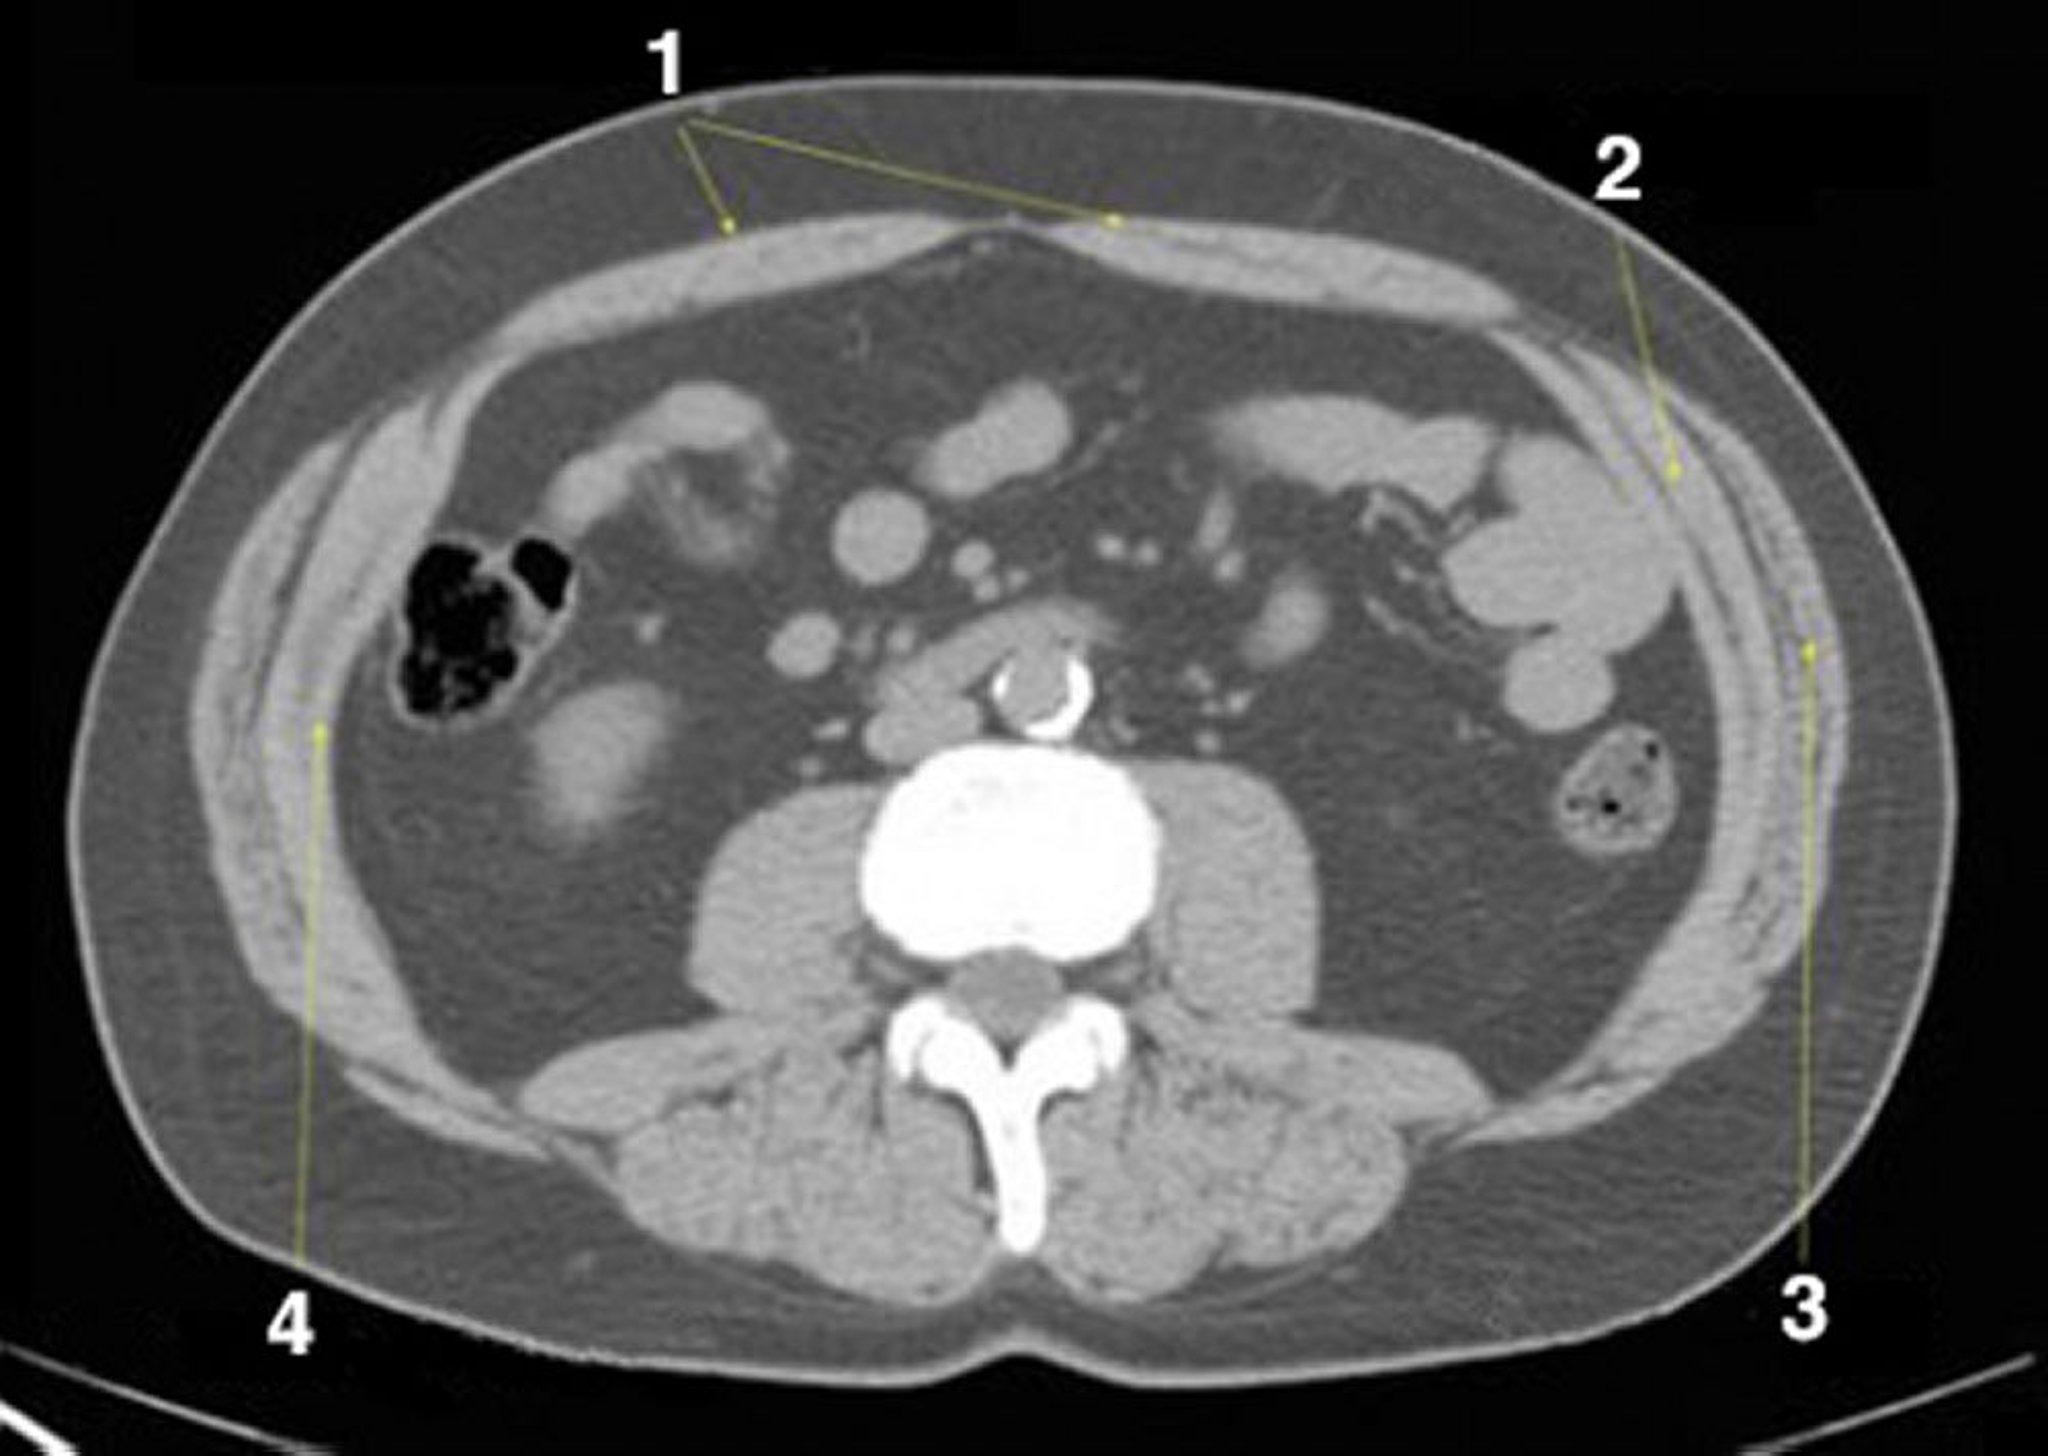

Phim chụp CT vùng bụng và vùng chậu không thuốc cản quang cho thấy giải phẫu bình thường (lát cắt 19)

1 = cơ bụng thẳng; 2 = cơ chéo trong; 3 = cơ chéo ngoài; 4 = cơ bụng ngang.